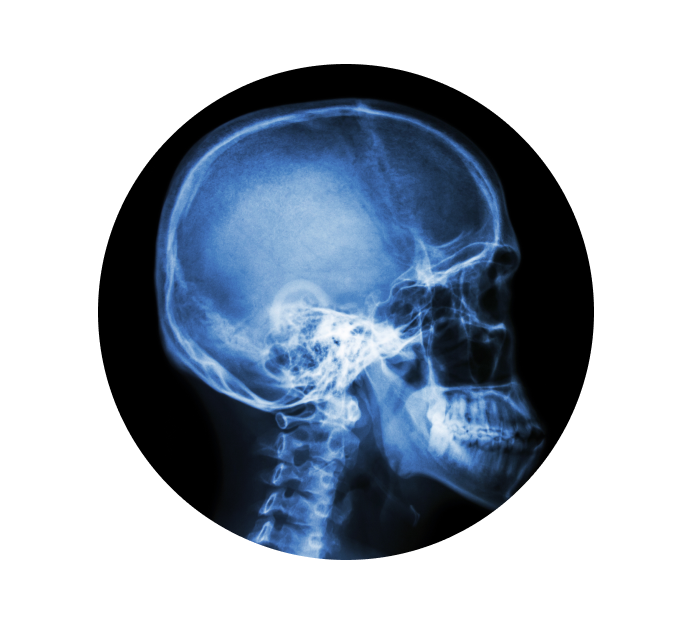

Рентген турецкого седла в Каменске-Уральском

Турецкое седло — это костное образование, которое находится в середине черепной коробки и защищает гипофиз (железа, вырабатывающая гормоны, участвующие в процессах обмена веществ, роста и развития человеческого организма). Рентген турецкого седла делается по назначению врача для того, чтобы определить присутствие патологий. Снимок может показать форму, структуру и размеры седла, что позволит доктору определить присутствие возможных заболеваний.